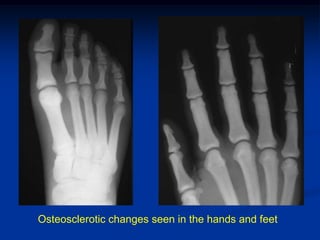

Case #3         Delayed Type Osteopetrosis

39 yr male with mild adult delayed type osteopetrosis with

transverse pathologic fracture left femur

Osteosclerotic changes seen in the hands and feet